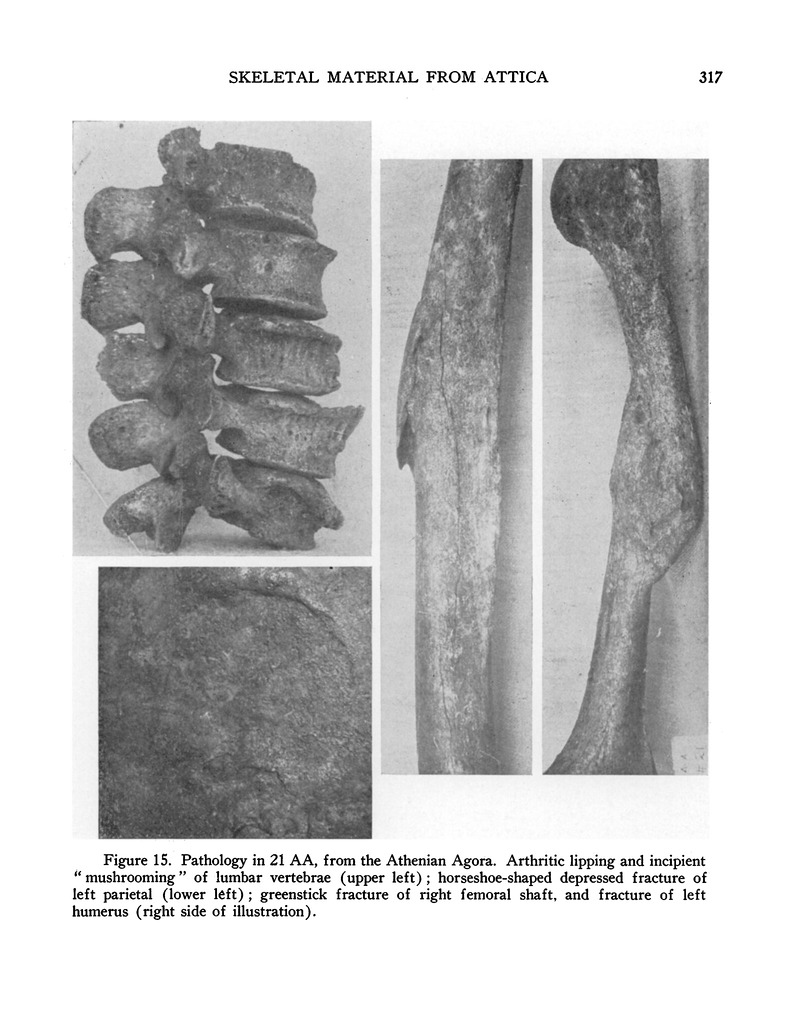

Publication Page: Hesperia 14.4, s. 41, p. 317